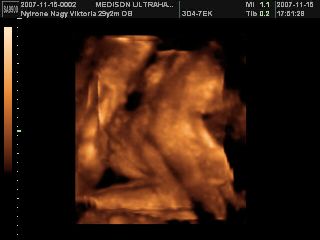

És van egy kis elmaradásom, mikor 4d-n voltunk nem tettem fel képeket, de most megvannak, szóval Eszti baba 25+3-nál:

és ennyi, mert ennyit láttunk összesen, hiába sétáltam, böködtem, nem mozdult el!